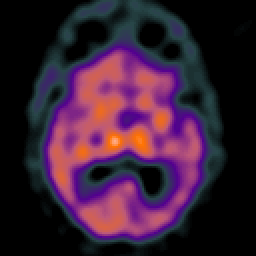

Subdural Hygroma,overlay -- Slice #23

[Home][Help][Clinical] Slice 23